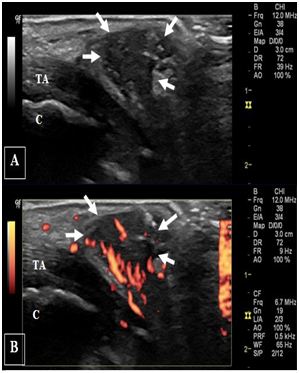

The ultrasonography demonstrated fragmentation of the apophysis of the calcaneus and an avulsed bone fragment at the insertion of the Achilles tendon (Figure 3) together a well-defined echogenic fluid collection with high Doppler signals on both sides of tendo-achilles (Figure 4). Ultrasonographic guided needle aspiration of the fluid collection was performed, the Culture of the aspirated fluid revealed Staphylococcus aureus. The X-ray showed Fragmentation of calcaneal apophysis & few osteolytic lesions (Figure 5). Echocardiography was normal. Further evacuation was done surgically and antibiotic was started with marked improvement of the patient condition.

Figure 3 legend   (A) Long-axis and (B)short-axis ultrasonography on right heal shows marked cortical irregularity and fragmentation of the posterior calcaneal surface (arrow head) and an avulsed bone fragment (arrow). (C) Long-axis and (D) short-axis ultrasonography on left asymptomatic heal for comparison; note the almost smooth cortical calcaneal surface with subtle irregularity. TA: tendoachieles; C: calcaneal bone.

Figure 4 legend   (A) Gray-scale and (B) power Doppler long-axis ultrasonography on right heal show well delineated soft tissue collection (arrows) on the side of tendoachiles with increased vascularity. (C) & (D) represent gray-scale and power Doppler short-axis views respectively on the soft tissue collection. TA: tendoachieles; C: calcaneal bone.